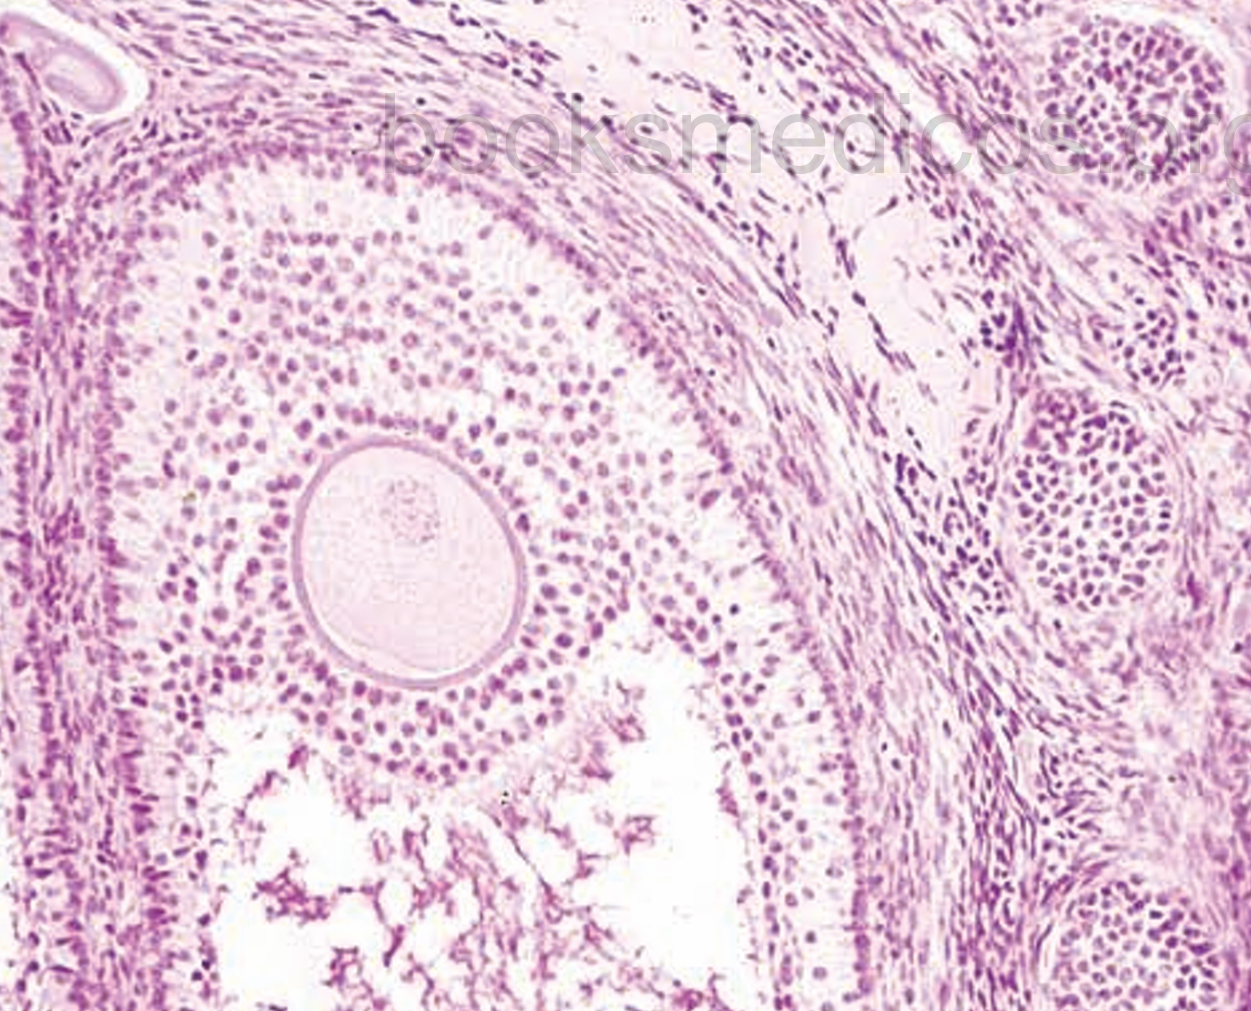

En la zona cortical del ovario existen una serie de elementos que experimentan modificaciones cíclicas durante la vida de la mujer y que constituyen la dotación germinal. Estas formaciones reciben distintos nombres, según su estadio evolutivo: folículos primordiales, folículos en maduración, folículos de De Graaf, cuerpos lúteos, corpus albicans, folículos atrésicos y folículos fibrosos. La constitución histológica de estos elementos varía de unos a otros.

En la zona medular del ovario se observan abundantes vasos y, en ocasiones, ciertas formaciones, tales como la rete ovarii, procedente de invaginaciones primitivas del epitelio germinal. Estas formaciones están constituidas por elementos tubulares, revestidos de un epitelio cúbico o cilíndrico con proyecciones polipoides intraluminales. Son restos embrionarios de origen wolffiano.